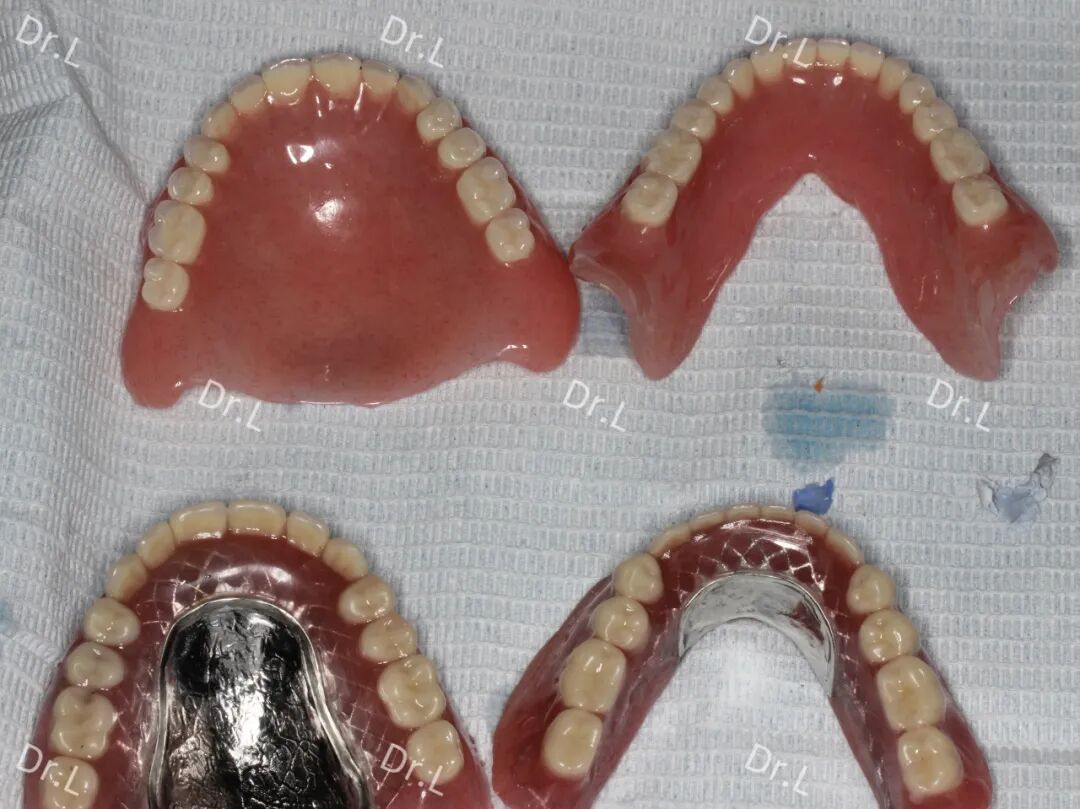

吸附性义齿制作流程(部分)

成品

吸附性全口义齿(上)与普通全口义齿(下)对比——更轻便 异物感小

经综合考虑各方面因素,口腔科主任李俊与H爷爷及其家属耐心沟通,建议他放弃制作普通全口义齿而制作全口吸附性义齿(BPS), 了解了吸附性义齿的特点后,H爷爷选择进行BPS修复。第二日上午10时,H爷爷来到口腔科开始制作全口吸附性义齿,经技工反复取模、修整模型、排牙、去蜡充胶等制作程序,当天下午18时,一副崭新的上下颌全口吸附性义齿制作完成。当H爷爷带上全口吸附性义齿后,无需调磨,美观的排牙,牢固的固位,有效的咀嚼让他顿时露出了满意的笑容!